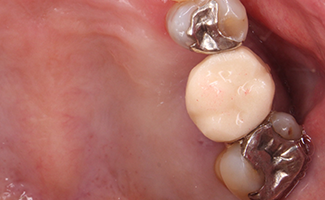

BEFORE

AFTER

BEFORE

AFTER

高い審美性を持つ高品質樹脂でできた歯冠修復物です。天然歯より柔らかい材料なので、噛み合う他の歯を傷つけるなどの心配がないことが特徴です。基本的にダイレクトボンディング治療ができない比較的大きな虫歯が適応となります。

BEFORE

AFTER

BEFORE

AFTER

BEFORE

AFTER

BEFORE

AFTER

BEFORE

AFTER

透明感が高く、審美性に優れ、天然歯が持つ自然な美しさをそのまま再現することができる次世代のセラミックです。

従来のセラミックに比べ、強度が高く、その優れた特性で、我々の業界でも高く評価されています。

金属を一切使用しませんので、「ブラックマージン」といわれる現象(かぶせ物と歯の境目に見られる黒い線)が起こることもなく、金属のイオン化による歯ぐきの黒ずみも起こりません。また最近では、人工ダイヤといわれる「ジルコニア」を使用し、耐久性をさらに向上させたものもあります。